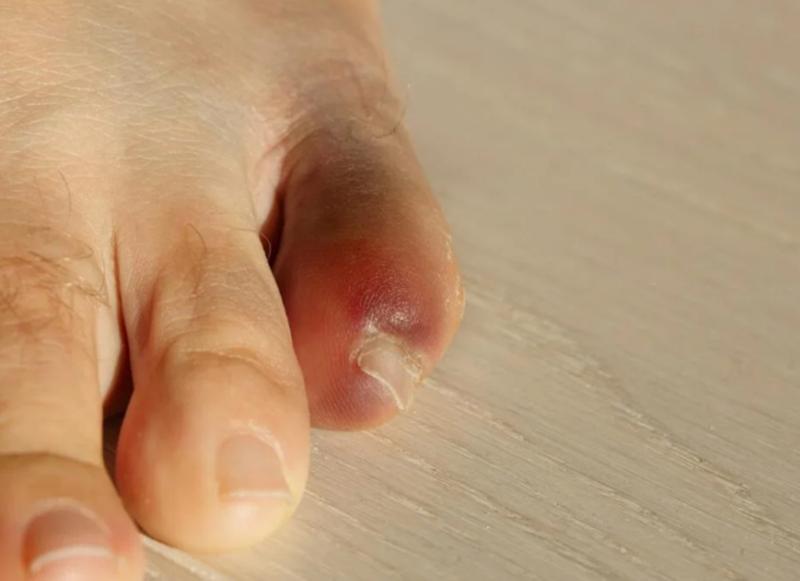

中到重度的扭伤可能和骨折难以分辨,都会出现肿胀、淤青,脚趾难以移动,站立和行走困难。尤其 撕脱性骨折 和应力性骨折,没有明显的外伤,容易和扭伤混淆。 撕脱性骨折是指一小块骨片被肌肉或者韧带从骨头上撕下来, 会出现肿胀、瘀伤以及脚趾关节活动困难。有时可能被误诊为扭伤,甚至采取了错误的治疗。

- 脚趾上某个地方严重变色

- 有脱臼的迹象,脚趾看起来和以前不一样。

- 严重疼痛、肿胀或淤青。

- 脚趾看起来畸形。